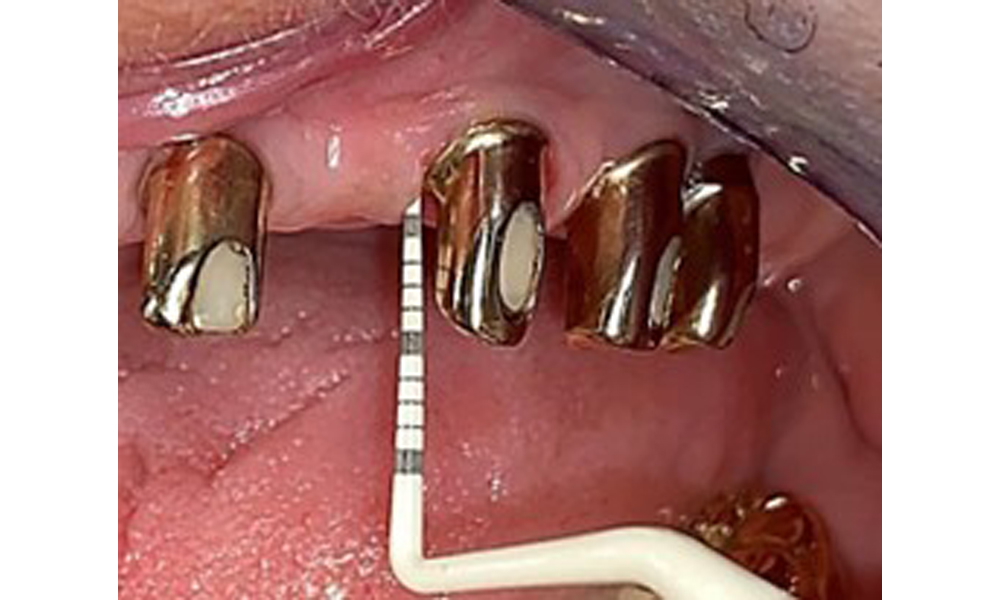

Occlusal view: Maxilla with tooth and implant-supported telescopic prostheses.

Fig. 2: Occlusal view: Maxilla with tooth and implant-supported telescopic prostheses